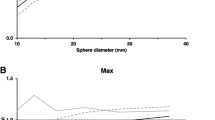

It is also possible to observe an average percentage variation of SUVmax and SUVmean higher for findings ≤ 10 mm (p < 0.001) and > 10 mm (p < 0.01), while there are no statistically significant differences (p > 0.1) for findings > 20 mm (see Graph 1a–c).

As for the background, compared to OSEM, Q.Clear + TOF showed a statistically significant SUV variation in those findings with medium (e.g., mediastinal lymph nodes, p < 0.005) and low backgrounds (p < 0.05), while there were not significant differences for those with high background (e.g., a lesion localized in the liver parenchyma, p > 0.1). Furthermore, the mean percentage variations of SUVmax and SUVmean of the liver relative to all the scans examined are, respectively, − 0.1 and 0.2, therefore not significant (p > 0.1).